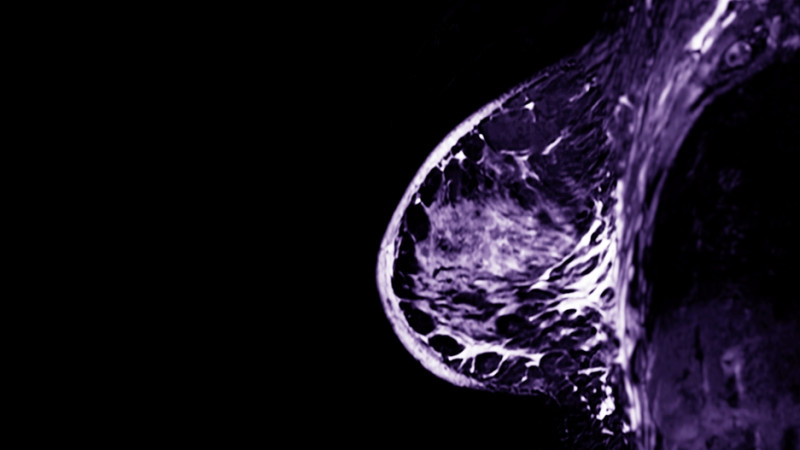

Le cancer de l’endomètre concerne la muqueuse interne de l’utérus. Il est le plus courant et généralement diagnostiqué à un stade précoce, ce qui améliore nettement le pronostic.

Ce type de cancer est souvent dû à une infection persistante par le papillomavirus humain (HPV). Il se développe plus lentement et peut être détecté grâce au frottis de dépistage ou au test HPV.